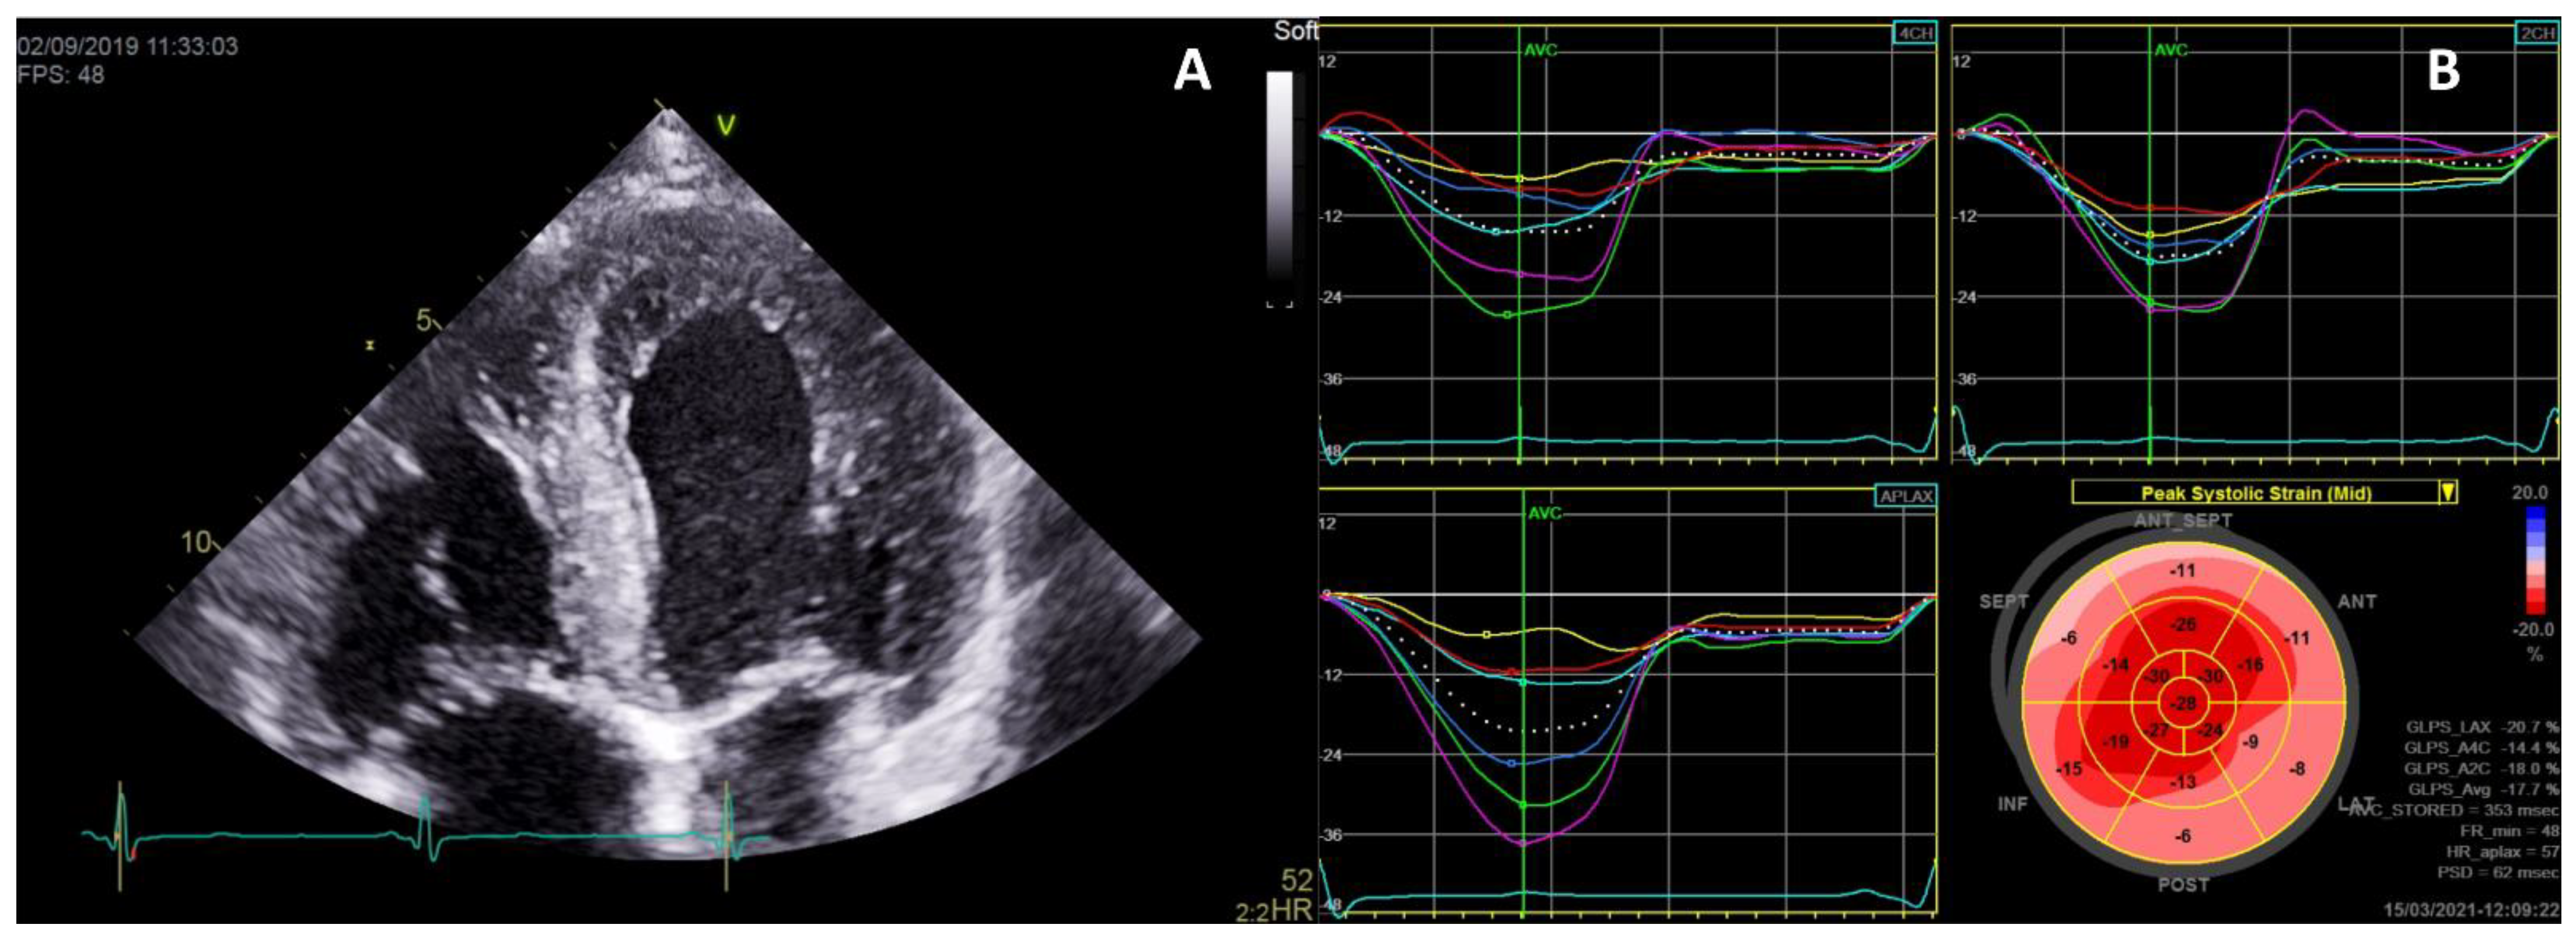

- Krämer, J.; Niemann, M.; Liu, D.; Hu, K.; Machann, W.; Beer, M.; Wanner, C.; Ertl, G.; Weidemann, F. Two-dimensional speckle tracking as a non-invasive tool for identification of myocardial fibrosis in Fabry disease. Eur. Heart J. 2013, 34, 1587–1596. [Google Scholar] [CrossRef] [Green Version]

- Vijapurapu, R.; Nordin, S.; Baig, S.; Liu, B.; Rosmini, S.; Augusto, J.; Tchan, M.; A Hughes, D.; Geberhiwot, T.; Moon, J.C.; et al. Global longitudinal strain, myocardial storage and hypertrophy in Fabry disease. Heart 2018, 105, 470–476. [Google Scholar] [CrossRef]

- Saccheri, M.C.; Cianciulli, T.F.; Lax, J.A.; Gagliardi, J.A.; Cáceres, G.L.; Quarin, A.E.; Kisinovsky, I.; Rozenfeld, P.A.; Reisin, R.C. Aadelfa Two-Dimensional Speckle Tracking Echocardiography for Early Detection of Myocardial Damage in Young Patients with Fabry Disease. Echocardiography 2013, 30. [Google Scholar] [CrossRef]

- Zada, M.; Lo, Q.; Boyd, A.C.; Bradley, S.; Devine, K.; Denaro, C.P.; Sadick, N.; Richards, D.A.; Tchan, M.C.; Thomas, L. Basal Segmental Longitudinal Strain: A Marker of Subclinical Myocardial Involvement in Anderson-Fabry Disease. J. Am. Soc. Echocardiogr. 2020, 24. [Google Scholar] [CrossRef]

- Shanks, M.; Thompson, R.B.; Paterson, I.D.; Putko, B.; Khan, A.; Chan, A.; Becher, H.; Oudit, G.Y. Systolic and Diastolic Function Assessment in Fabry Disease Patients Using Speckle-Tracking Imaging and Comparison with Conventional Echocardiographic Measurements. J. Am. Soc. Echocardiogr. 2013, 26, 1407–1414. [Google Scholar] [CrossRef] [PubMed]

- Réant, P.; Testet, E.; Reynaud, A.; Bourque, C.; Michaud, M.; Rooryck, C.; Goizet, C.; Lacombe, D.; De-Précigout, V.; Peyrou, J.; et al. Characterization of Fabry Disease cardiac involvement according to longitudinal strain, cardiometabolic exercise test, and T1 mapping. Int. J. Cardiovasc. Imaging 2020, 36, 1333–1342. [Google Scholar] [CrossRef] [PubMed]

- Gruner, C.; Verocai, F.; Carasso, S.; Vannan, M.A.; Jamorski, M.; Clarke, J.T.; Care, M.; Iwanochko, R.M.; Rakowski, H. Systolic Myocardial Mechanics in Patients with Anderson-Fabry Disease with and without Left Ventricular Hypertrophy and in Comparison to Nonobstructive Hypertrophic Cardiomyopathy. Echocardiography 2012, 29, 810–817. [Google Scholar] [CrossRef] [PubMed]

- Visoiu, I.-S.; Ciobanu, A.O.; Nicula, A.I.; Iascone, M.; Jurcut, R.; Vinereanu, D.; Rimbas, R.C. Severe Late-Onset Fabry Cardiomyopathy Unmasked by a Multimodality Imaging Approach. Circ. Cardiovasc. Imaging 2019, 12, e009709. [Google Scholar] [CrossRef]